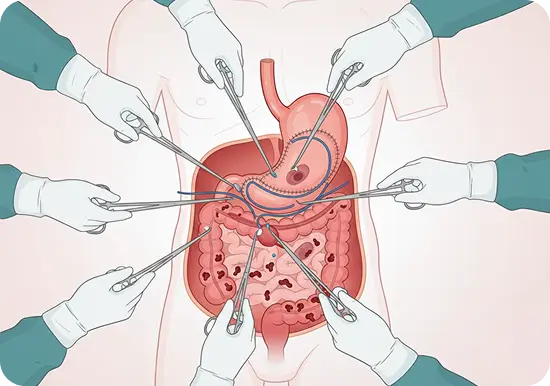

Benign GI Conditions

- Surgery for gastrointestinal stromal tumours (GISTs)

- Fundoplication for GERD and hiatal hernias

- Surgery for small bowel obstructions and diverticular disease

- Management of achalasia and esophageal motility disorders

Advanced Minimal Access Surgery

- Laparoscopic and robotic gastrointestinal surgeries

- Keyhole surgery for hernia repairs (inguinal, incisional, and diaphragmatic hernias)